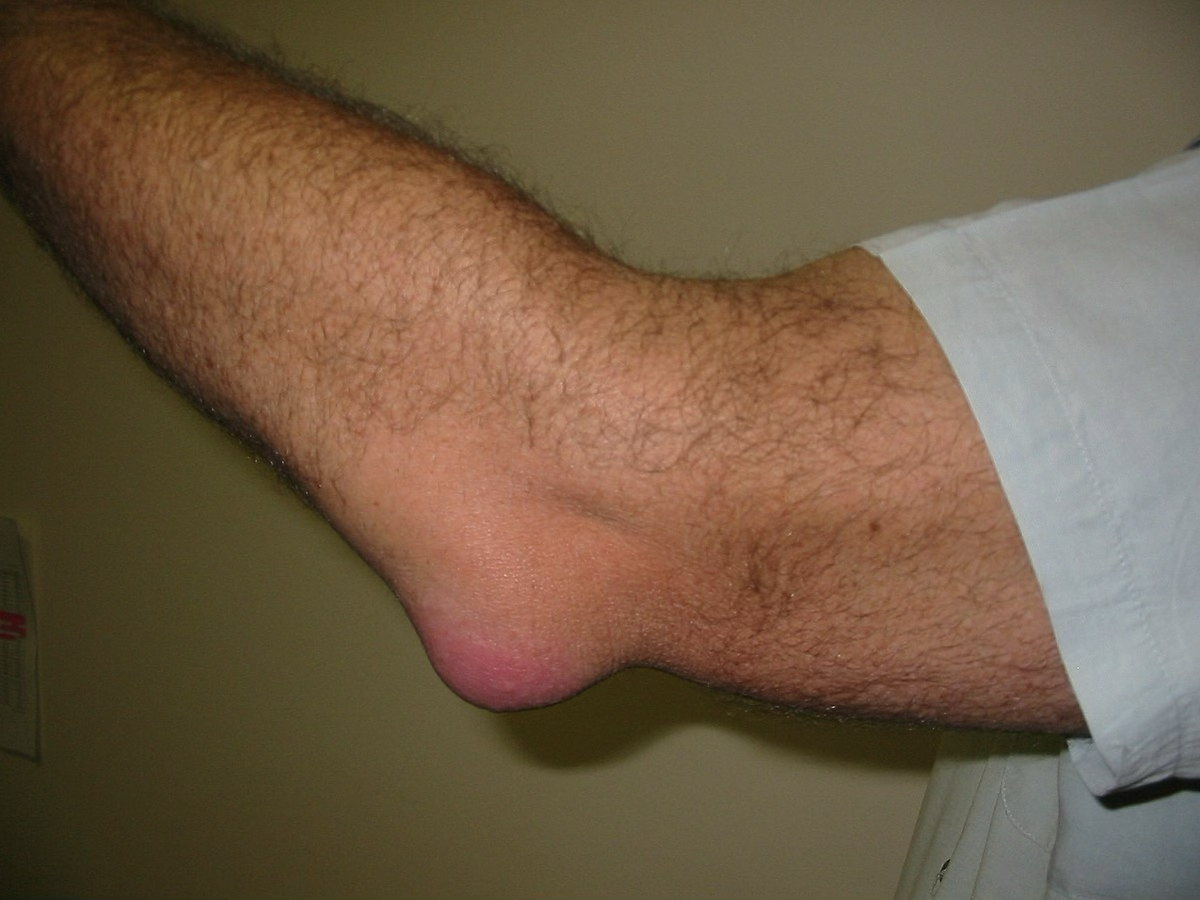

olecranon bursitis

superficial, so injuries occur most often with direct blows

symptoms: mild pain, pressure, swelling, being tender. tends to blow up and have little pain

treatment: compress and ice it. If swelling doesn’t resolve, can drain it. If an athlete, we tend to pad area so it doesn’t keep happening